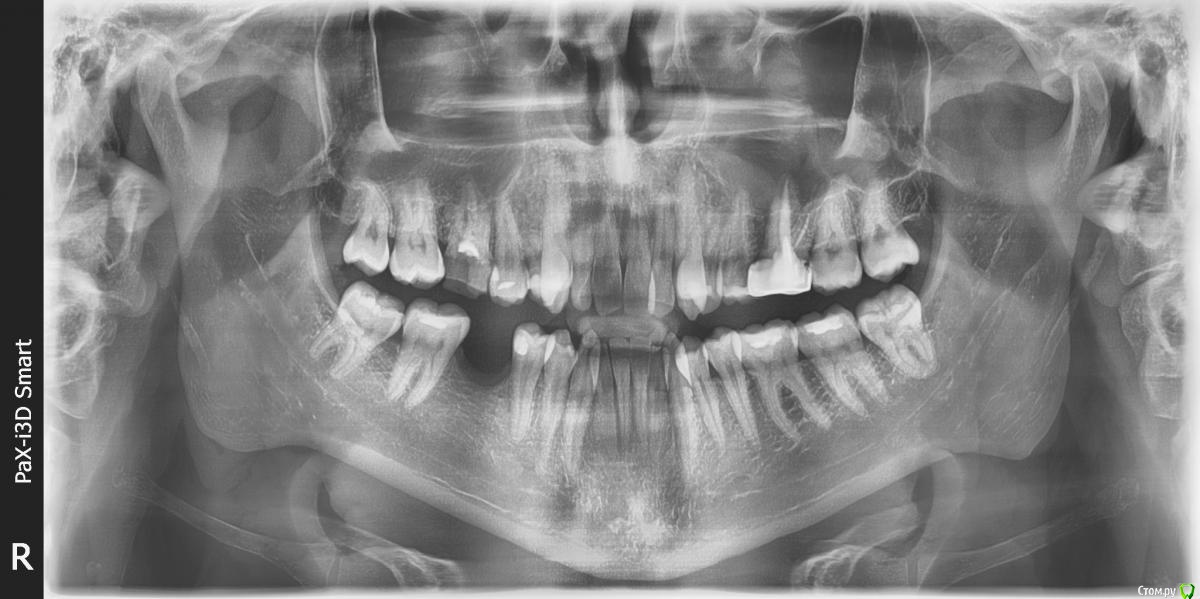

Баурсак Опубликовано 27 июня, 2017 Поделиться Опубликовано 27 июня, 2017 Здравствуйте, прошу помощи.Панарамный снимок сделан 14.04.2017, при планировании лечения зуба 25 (стоит пломба, чувствительность к холодному и горячему).Лечить еще не ходил и вот только собираюсь.Для надежности сегодня сходил и сделал снимки отдельных зубов, того же 25 и еще 16 (тоже планируется лечение, зуб мертвый и начал крошиться).На одиночном снимке зуба 16 видна какая то темная область (снимали его два раза для исключения ошибки). Я очень переживаю, на апрельском снимке темной зоны не видно. Десна в том месте не болит, зуб 16 потемневший, рядом с десной имеет темное обрамление.Подскажите пожалуйста что на снимке? Ссылка на комментарий

shishok Опубликовано 27 июня, 2017 Поделиться Опубликовано 27 июня, 2017 На отдельных снимках наслаивается проекция гайморовой пазухи. Ссылка на комментарий